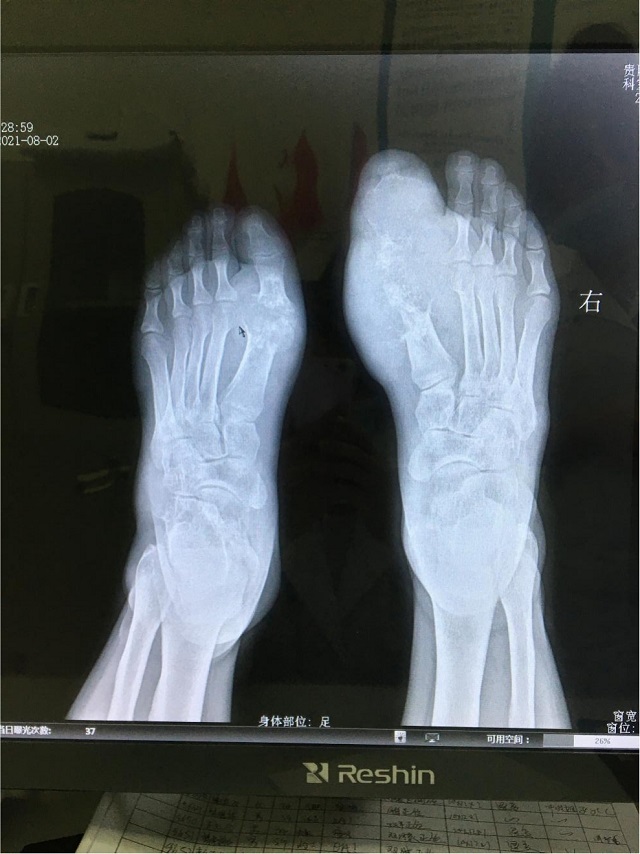

尿酸是人體代謝嘌呤的產(chǎn)物,正常情況下,人體內(nèi)尿酸的生成與排出基本平衡,但當(dāng)一個人的代謝功能出現(xiàn)異常時,高嘌呤的食物會讓體內(nèi)產(chǎn)生更多的尿酸,破壞這種平衡,導(dǎo)致體內(nèi)出現(xiàn)尿酸過多。當(dāng)血液中的尿酸過多,達(dá)到飽和狀態(tài),就會產(chǎn)生結(jié)晶。這些結(jié)晶容易沉積在腳踝、腳趾等關(guān)節(jié)部位,誘發(fā)局部炎癥,表現(xiàn)出腫痛。這種由于尿酸鹽結(jié)晶沉積而帶來出來的癥狀,就是痛風(fēng)。簡單來說,高尿酸血癥是痛風(fēng)的一個誘因,“痛風(fēng)”是一種嚴(yán)重的癥狀,有高尿酸血癥不一定會痛風(fēng)。

不愛吃海鮮,也很少喝酒,基本上不喝碳酸飲料,父母都沒有痛風(fēng)病史,那小伙子的痛風(fēng)由何而來?交流會現(xiàn)場來了一位痛風(fēng)患者,朱紅梅主任向大家展示了這位患者手術(shù)的一些圖片,其中有一張就是小伙子在做水筋針治療時從關(guān)節(jié)腔里擠出來的像牙膏一樣的液狀痛風(fēng)石。

接診過程中朱紅梅主任了解后發(fā)現(xiàn),小伙子偏好的飲食是牛肉、豬肉、雞肉,雖然少吃海鮮,喝酒喝碳酸飲料較少,但較少運(yùn)動,所以他的尿酸高主要與個人的體質(zhì)因素有關(guān),即內(nèi)源性的尿酸生成多,轉(zhuǎn)化、排泄少,導(dǎo)致大量痛風(fēng)結(jié)晶沉積。

通過痛風(fēng)石切除術(shù)、中醫(yī)微創(chuàng)可視針刀鏡關(guān)節(jié)清理術(shù)以及水筋針手術(shù)清理后,輔助一系列中醫(yī)特色理療,患者坐著輪椅來院,現(xiàn)在不僅雙足大腳趾得以保全,行動與正常人差別并不大,活動范圍改善了很多。小伙子為表示對朱院長的感謝,現(xiàn)場還向朱院長贈送了錦旗。